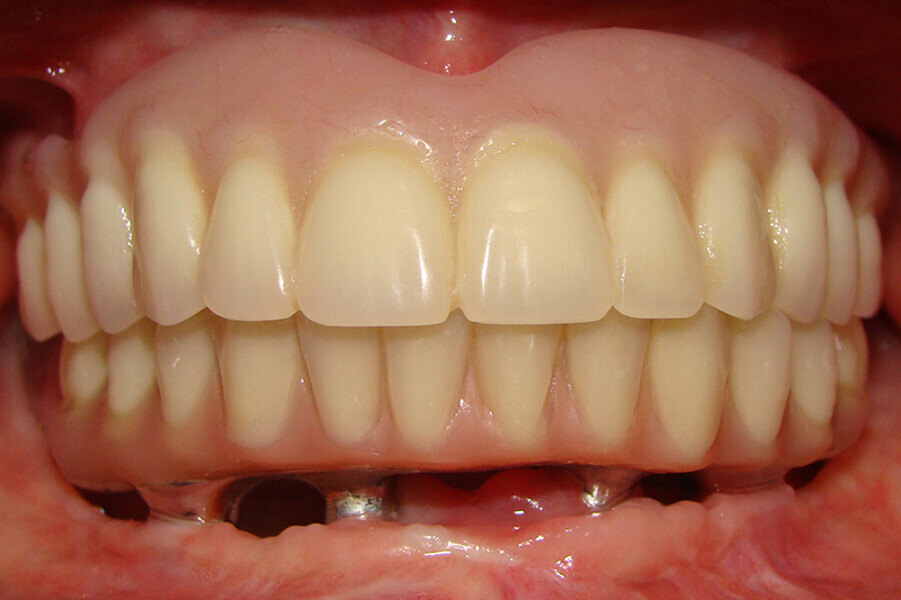

Fig. 4 Prótesis Híbrida inmediata y radiografía control con 6 años post-operatorio

Fig. 5. Prótesis Híbrida inmediata y radiografía control con 6 años post-operatorio